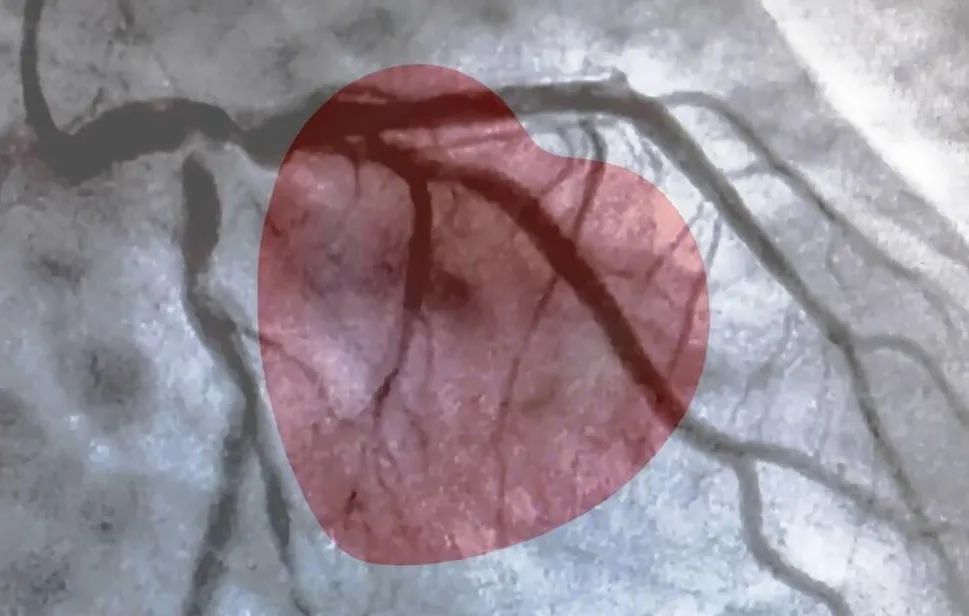

晚上10:30,医院急诊,给张先生做完心电图,提示ST段抬高,这是典型的心肌梗死。结合患者胸痛大汗的表现,诊断为心肌梗死,马上送进导管室进行造影检查。

晚上11:00,张先生造影结果:血管完全正常,可见局限性斑块,没有明确的狭窄,没有血栓,没有闭塞,没有缺失。

心脏是怎么固定的男子心肌梗死,检查血管没有狭窄,没有闭塞_https://www.jmylbn.com_新闻资讯_第2张这是什么原因呢?